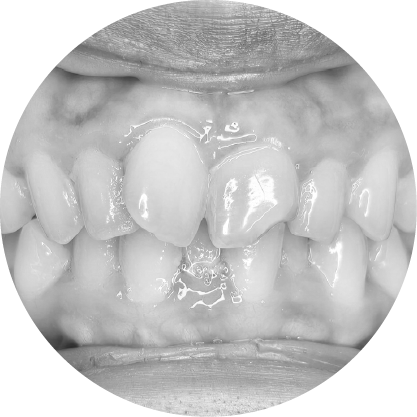

ฟันสบล่างคือภาวะที่ฟันล่างยื่นออกมามากกว่าฟันบน ซึ่งมักส่งผลต่อการเคี้ยวอาหารและความสมดุลของใบหน้า การจัดฟันสามารถช่วยปรับแนวขากรรไกรให้ถูกต้อง ช่วยเพิ่มทั้งประสิทธิภาพในการใช้งานและความสวยงามของใบหน้า

ตัวอย่างในชีวิตจริง